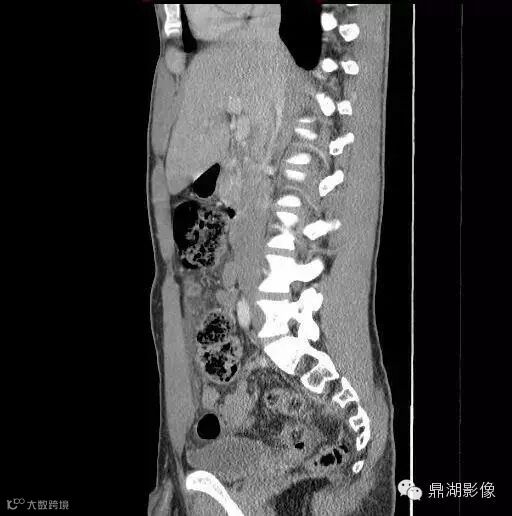

18岁男性,腹痛,定位模糊,无直肠出血。

影像学描述

诊断

Meckel憩室炎 Meckel's diverticulitis

典型的位置位于下腹部(少数盆腔内)中线附近(67%),尤其是肚脐附近是其典型位置,病变与肚脐关系密切尤其是可见纤维索相连高度提示为Meckel's 憩室炎。发生于回肠肠系膜对侧,距回盲瓣50-60cm以内。

肠系膜炎性改变常较显著,表现为系膜密度增高及周围脂肪内条索状影,部分可伴腹水。

憩室壁常增厚,增强后绝大多数可见粘膜面强化。